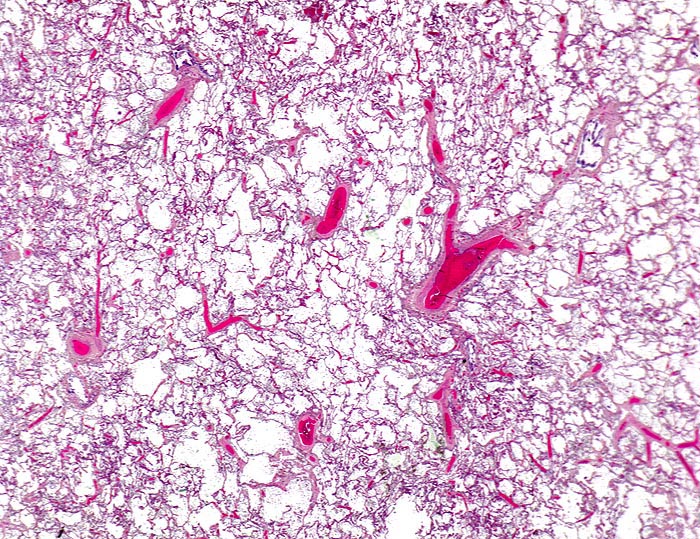

In einer frühen Phase kommt es zur roten Stauungsinduration, welche in eine braune Stauungsinduration übergeht. Die Eindrückbarkeit der Lungen ist aufgrund der Fibrosierung der Alveolarsepten vermindert. Die meist fleckförmige braune Verfärbung beruht auf der Anhäufung von hämosiderinhaltigen Herzfehlerzellen in den Alveolarlichtungen. Makrophagen in den Alveolarlichtungen phagozytieren die ausgetretenen Erythrozyten. Der Nachweis von Erythrozyten im Zytoplasma von Makrophagen spricht für eine frische Blutung. Nach 3-5 Tagen ist in den Makrophagen Hämosiderin nachweisbar. Das Hämosiderin lässt sich mittels Eisenfärbung (Berliner-Blau) zuverlässig von Staubpigment abgrenzen. Als sicheres Zeichen für eine ältere Blutung gelten >20% hämosiderinspeichernde Makrophagen in der bronchoalveolären Lavage (BAL). Die hämosiderinhaltigen Alveolarmakrophagen werden auch Herzfehlerzellen genannt, da sie gehäuft im Rahmen einer linkskardialen Stauung bei Mitralklappenstenose auftreten.

Morphologische Merkmale:

• Mediahypertrophie der Pulmonalvenen.

• Fibrosierung und Verdickung der Alveolarsepten.